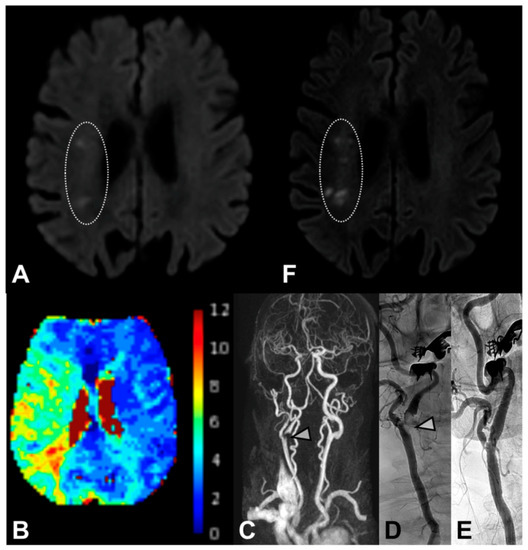

3.2. Clinical and DWI Outcomes

4.1. DWI Lesions